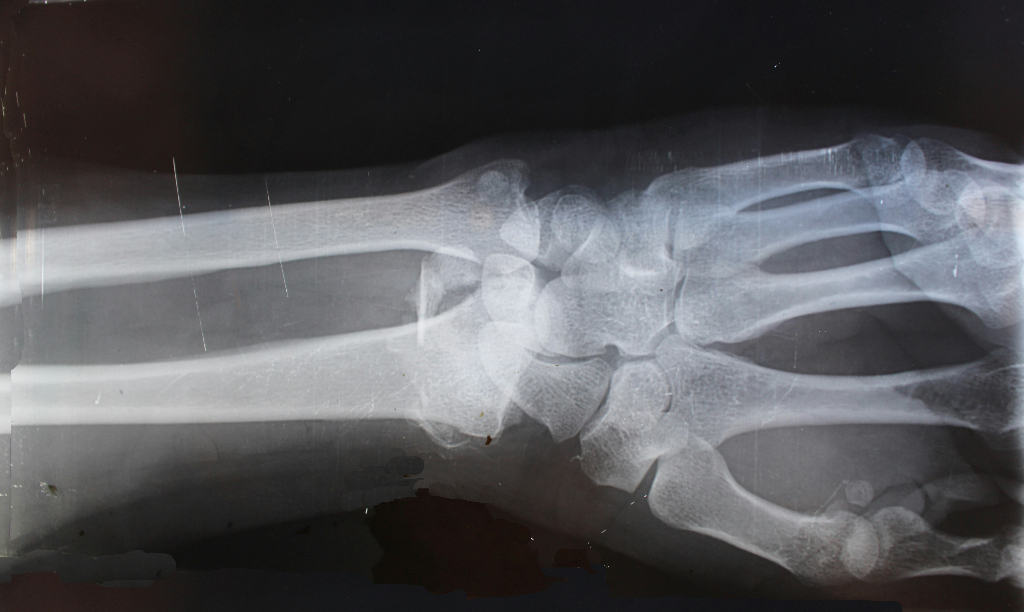

To test whether these effects occur in humans, the team conducted a small randomized trial involving 20 adults aged 50 to 75 with both obesity and osteoarthritis. Participants were divided into two groups: one received a standard joint-lubricating treatment, and the other received that same treatment plus semaglutide. After 24 weeks, those in the semaglutide group reported less pain and improved knee function. MRI scans showed thicker cartilage and signs of new growth in weight-bearing areas of the joint.